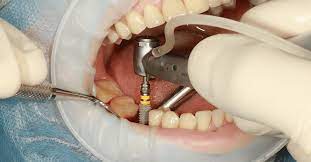

El siguiente paso es la intervención quirúrgica o cirugía de implantes dentales.

- La propia cirugía dental (primera fase quirúrgica)

En la primera fase de cirugía se realiza la colocación del implante dental en la mandíbula o en el hueso maxilar.

El paciente es anestesiado por lo que no sentirá ningún dolor durante el proceso completo para colocar implantes dentales.

La cirugía con implantes requiere sólo de anestesia local y la duración suele ser desde los 30 minutos hasta las 2 horas aproximadamente, dependiendo del número de implantes que vayan a colocar.